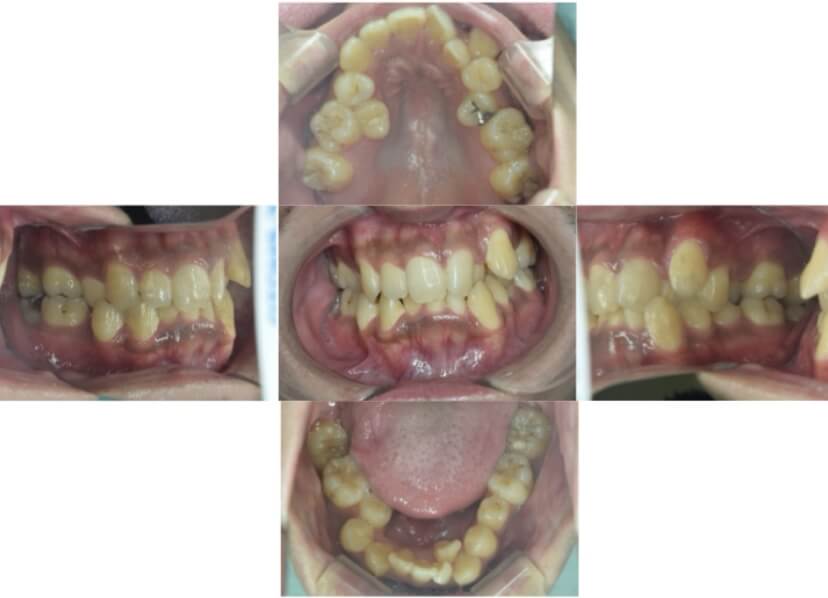

BEFORE

AFTER

症例3

叢生

抜歯

ブラケット矯正

上下顎叢生(上下の前歯のガタガタ)のケースです。

装置はラビアル(上下表側)で、上下顎の小臼歯を4本抜歯を行っています。抜歯したスペースを使って、上下の前歯の後方移動と叢生(ガタガタ)の改善を行っています。

主訴 八重歯を治したい。

年齢・性別 25歳 女性

お住まいの地域 神奈川県川崎市

治療方針 抜歯スペースを利用して上前歯の叢生(ガタガタ)の改善

抜歯部位 上下顎左右第一小臼歯

使用装置 ラビアル(上下表側)、顎間ゴム

治療期間 1年11か月

治療回数 16回

リテーナー クリアリテーナー